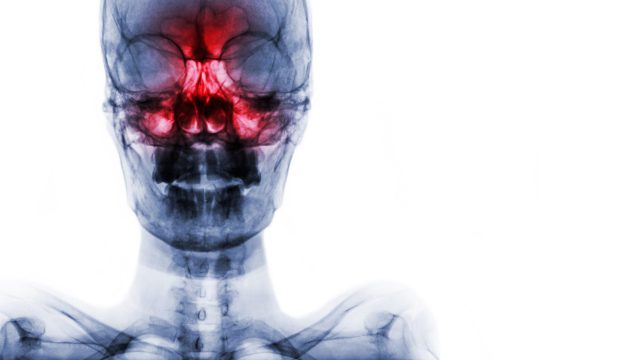

K rýmě se může přidružit například zánět vedlejších nosních dutin neboli sinusitida. Nejčastěji je postižena dutina kosti čichové, tzv. čichové sklípky, zasažena může být také dutina kosti čelistní, kosti čelní či kosti klínové.

Nejvýraznějším příznakem zánětu dutin je velká bolet hlavy, případně zubů. Lékař infekci diagnostikuje poklepem nad postiženou dutinou, který bývá bolestivý. Onemocnění je doprovázeno sekrecí z nosu, často hnisavou.

Nemocný má zpravidla také postižený čich (naštěstí jen dočasně), horečku a může ho bolet i ucho. Diagnóza se potvrzuje RTG snímkem či ultrazvukem, léčí se antibiotiky.